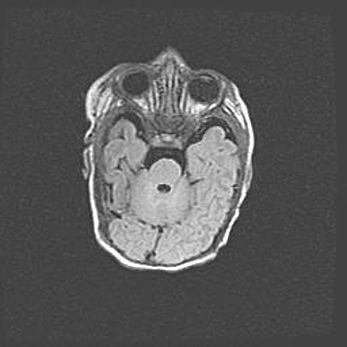

Лейкомаляция с кистозно-глиозной дегенерацией головного мозга.

Возраст: 2 месяца 25 дней

Вес: 6400 г

Окружность головы: 40 см

Срок гестации: 41 неделя

Лейкомаляцию относят к ишемически-гипоксическим повреждениям головного мозга, диагностируемым у новорожденных. При лейкомаляции в головном мозге обнаруживают очаги некроза, возникшие после тяжелой гипоксии и нарушения кровотока. В процессе морфогенеза очаги проходят три стадии: 1) развития некроза, 2) резорбции и 3) формирования глиозного рубца или кисты. Перивентрикулярная лейкомаляция (ПЛ) встречается примерно в 12% случаев среди новорожденных, обычно – у недоношенных детей, причем, частота ее зависит от массы, с которой младенец появился на свет. Наибольшее число малышей страдает лейкомаляцией, если масса при рождении 1500-2500 г.